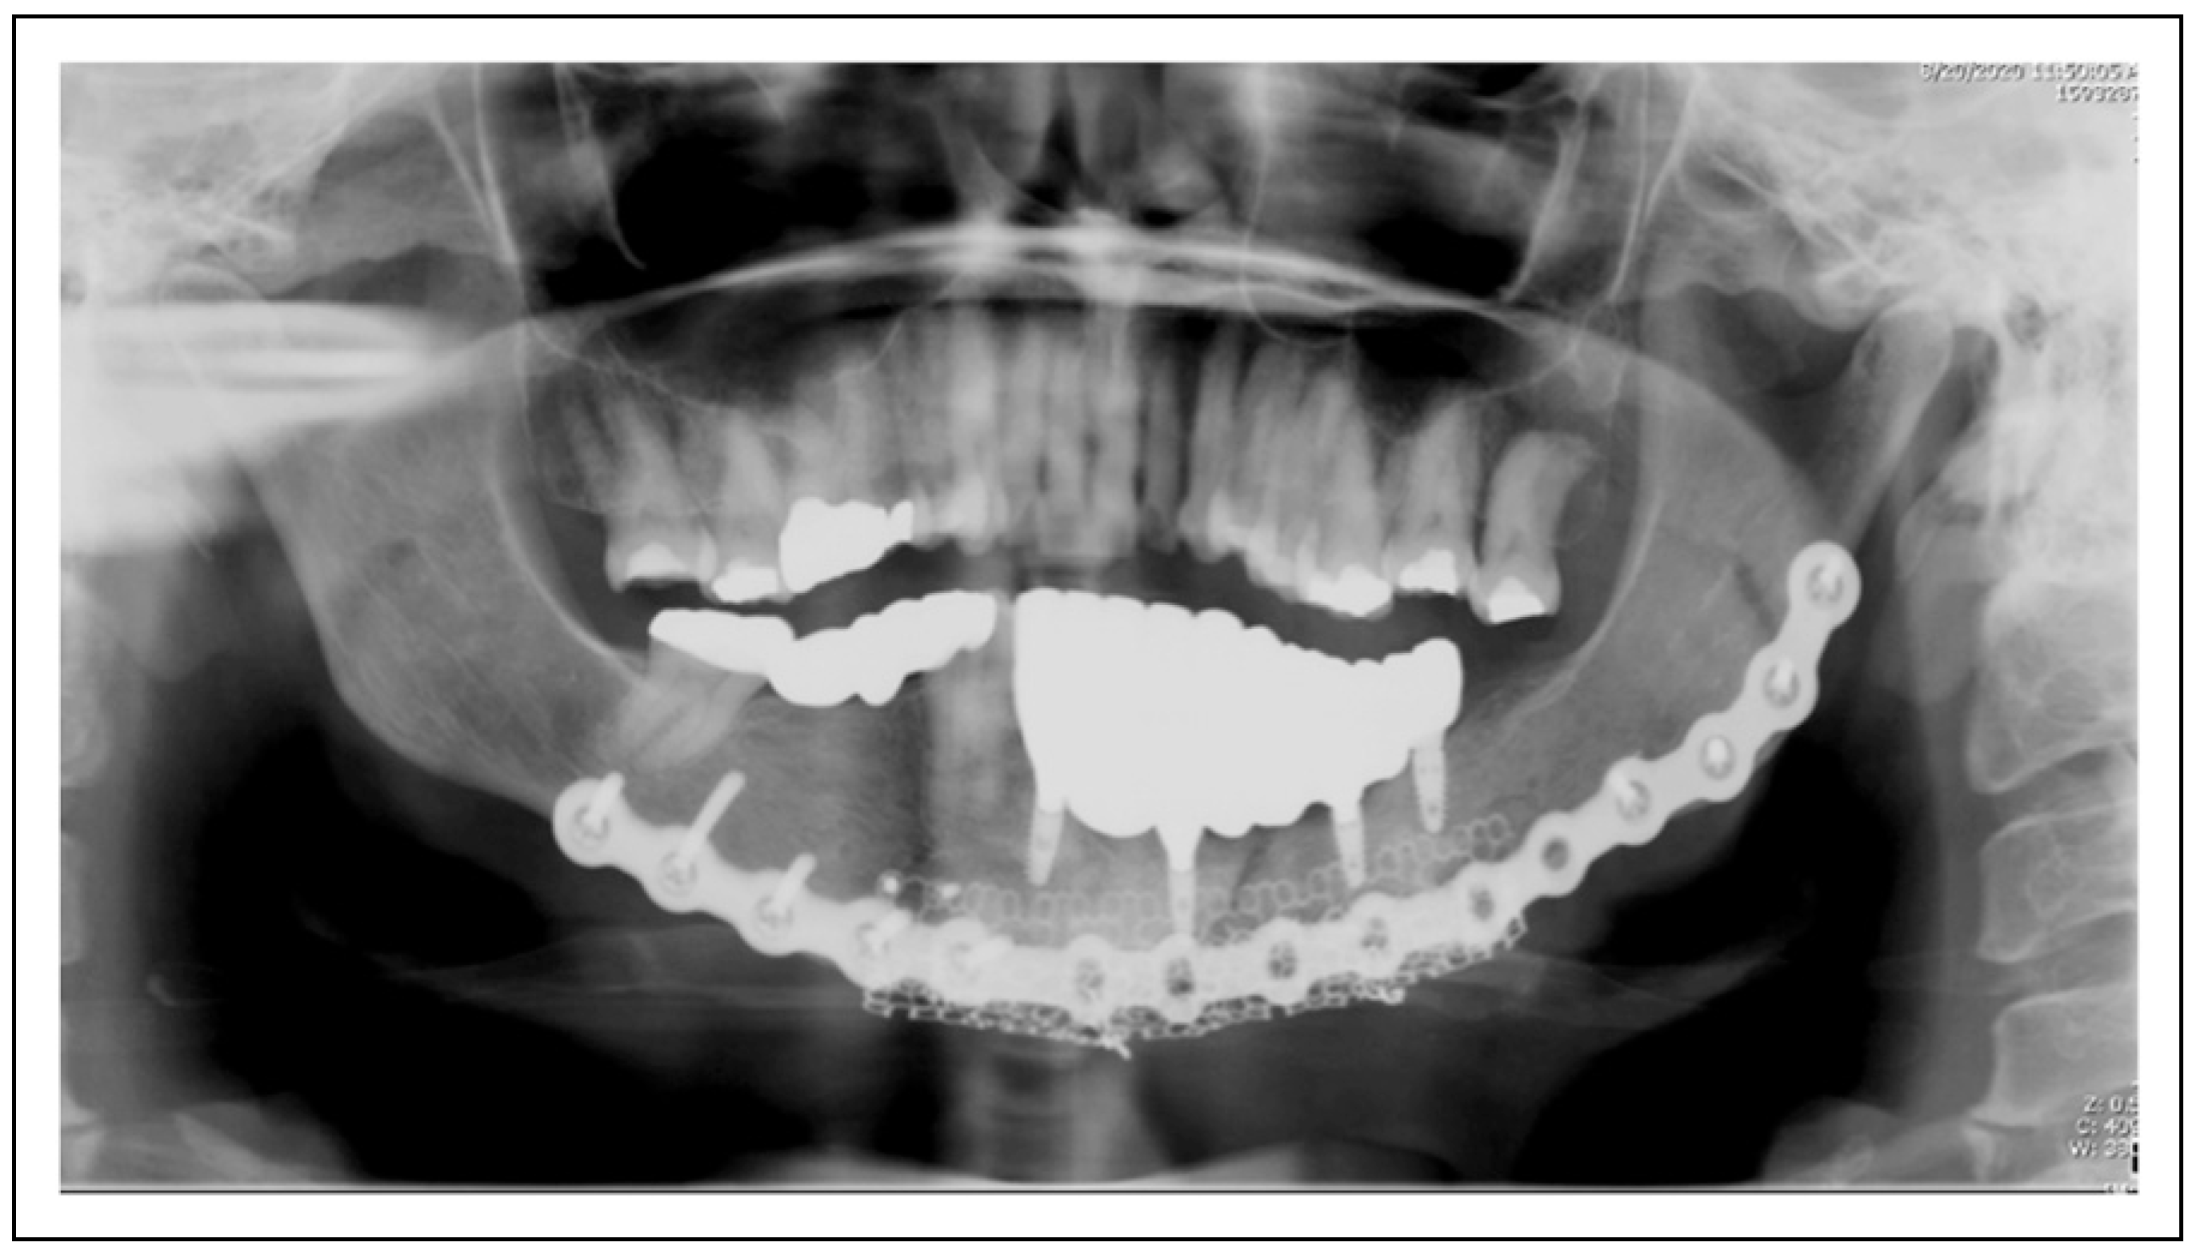

Figure 1.

Patient 2 is restored with 4 mandibular implants status post resection and reconstruction using tissue engineering techniques. These implants are without radiolucency or other signs of pathology 8 months post-operatively.